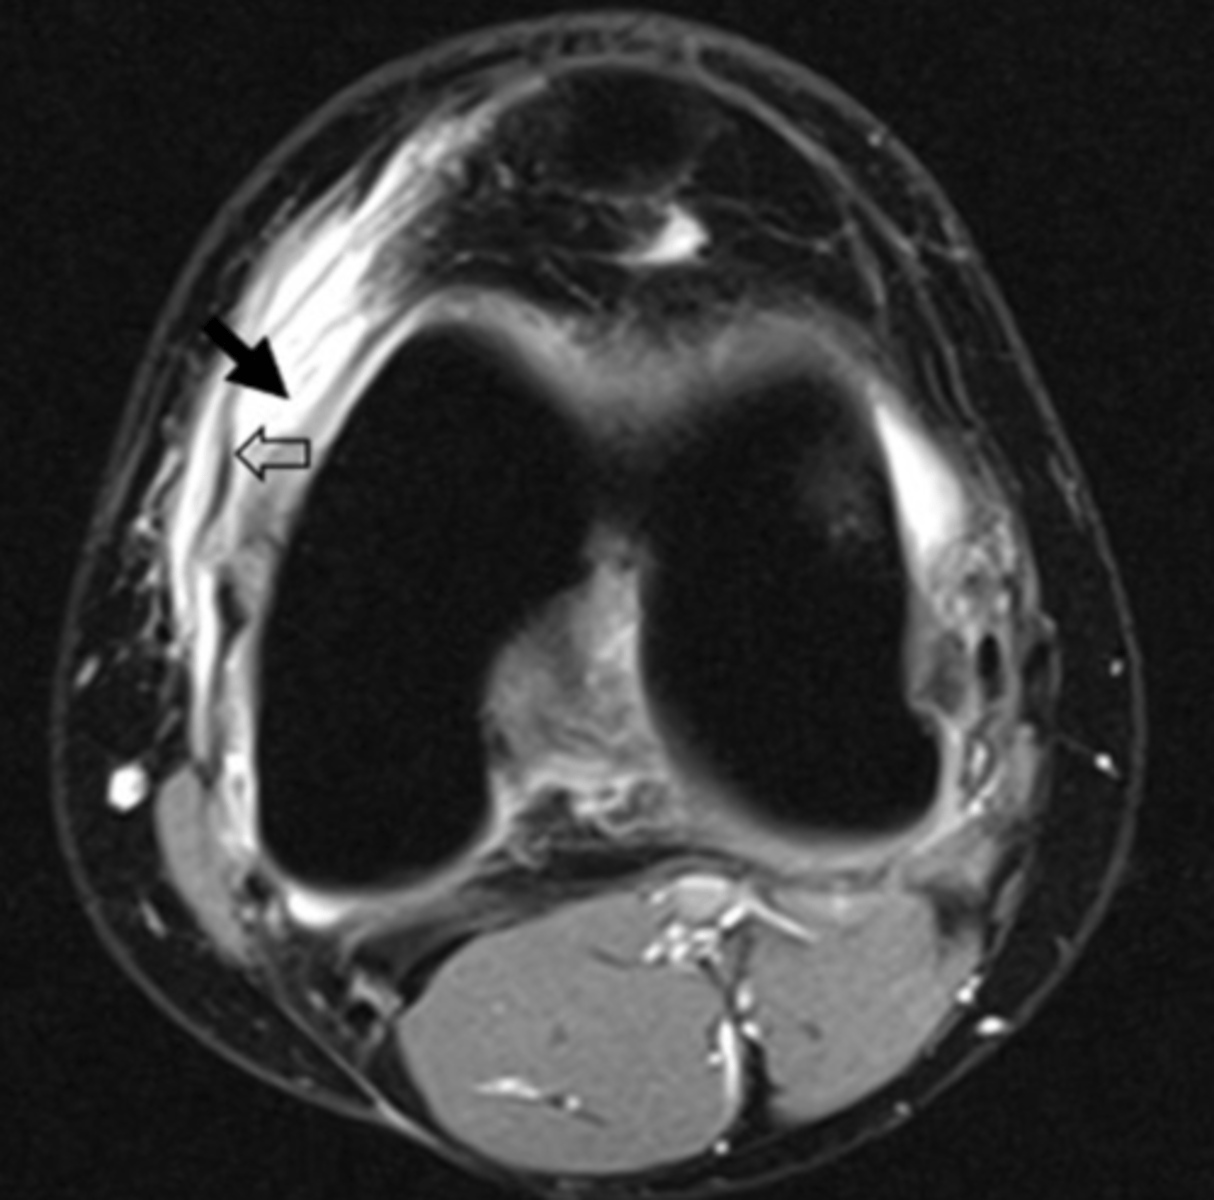

Synovial Fluid, T2 MRI

what does the S represent on this image and what type of image is this?

a. Swelling, T1 MRI

b. Sclerosis, T1 MRI

c. Synovial Fluid, T2 MRI

d. Sartorius, T2 MRI

sagittal

what is the view of this image?

a. coronal

b. axial

c. frontal

d. sagittal

bone bruise, T2 MRI

what can be seen on the medial tibial plateau in this image and what type of image is this?

a. tumor, T1 MRI

b. complex fracture, CT scan

c. bone bruise, T2 MRI

d. AVN, conventional radiograph

edema

This is an axial T2 image at the level of the femoral condyles. The open arrow points to the medial patellar retinaculum. What does the solid arrow point to?

a. Edema

b. Fatty tumor

c. Hemorrhage

d. Osteogenic tumor